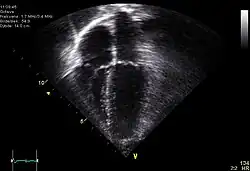

Echocardiogram is a study in which an ultrasound is used to exam the function of the heart. In Traumatic cardiac arrest, an echocardiogram may show ineffective motion of the heart and may provide clues that point to a specific cause of the arrest.